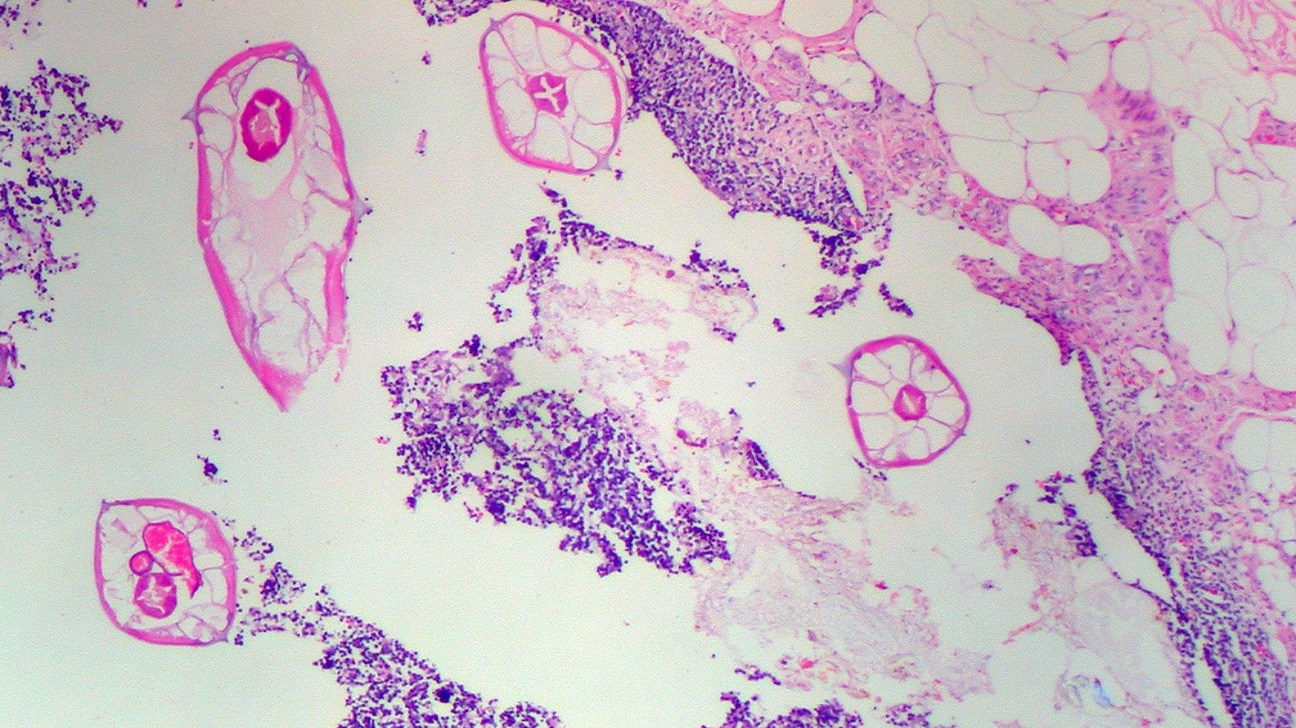

蟯蟲(Pinworms)

最常見的美國腸道蠕蟲感染類型高度傳染性症狀包括肛門區域劇烈瘙癢和刺激,睡眠不安和因肛門瘙癢引起的不適,

大便中的饒蟲可用“膠帶測試收集為醫院診所收集蟲卵在顯微鏡下進行檢查